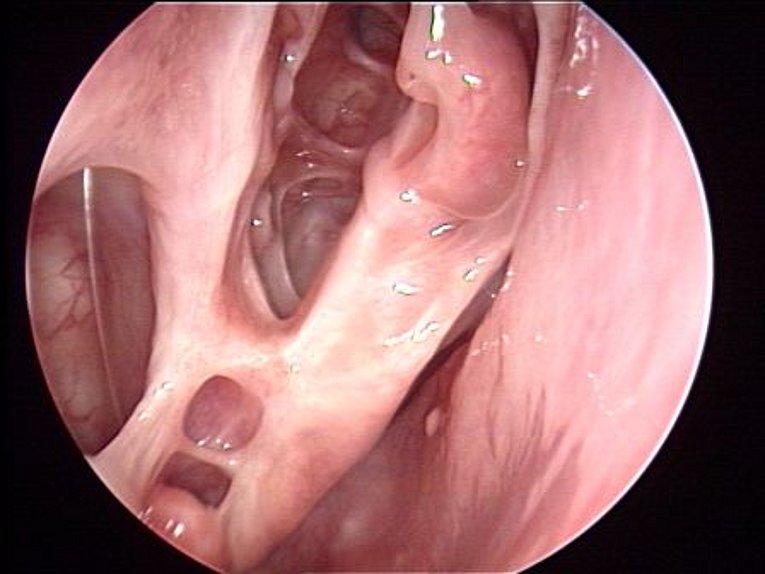

Immer mehr Patienten klagen über Beschwerden im Bereich der Nase und Nasennebenhöhlen, wie zum Beispiel behinderte Nasenatmung, verstärktes Naselaufen, Kopf- und Gesichtsschmerzen, Riechminderung und häufige Erkältungen. Untersucht man die Nase finden sich häufig entzündlich veränderte hyperplastisch-ödematöse Schleimhäute oder traubenförmige, glasig-transparente, blassgraue Schleimhautaussackungen. Diese Schleimhautaussackungen nennt man auch Nasenpolypen, Polyposis nasi oder polypöse Pansinusitis.

In der modernen Nasennebenhöhlenchirurgie wird versucht den krankhaften Prozess von der Nase aus zu sanieren und dabei die Funktion von Nase und Nasennebenhöhlen möglichst wenig zu beeinträchtigen. Hierzu werden optische Hilfsmittel wie Mikroskop und Endoskop sowie Spezialinstrumente, ggf. auch der Laser eingesetzt. Bei den entzündlichen Nebenhöhlenerkrankungen liegt das Hauptaugenmerk darauf, möglichst wenig eingreifend (minimal invasiv) vorzugehen, die Engstellen gezielt zu erweitern und gesunde Schleimhaut weitgehend zu erhalten. Der verbleibenden Schleimhaut wird so die Möglichkeit zur Erholung gegeben. An der Hals-Nasen-Ohren-Klinik der Universität Erlangen-Nürnberg wurde schon in den 70-iger Jahren von Prof. Wigand ein weltweit anerkanntes und verwendetes endoskopisch endonasales Konzept der Nasennebenhöhlenchirurgie entwickelt und intensiv sowohl klinisch als auch wissenschaftlich weiterentwickelt. Langzeituntersuchungen bestätigen den Erfolg dieser Methode sowohl durch langfristige Beschwerdelinderung bei ca. 80% aller operierten Patienten, als auch durch Besserung von asthmoiden Beschwerden, chronischen Bronchitiden und Infektanfälligkeit. Aber nicht nur bei der Behandlung von chronisch entzündlichen Erkrankungen der Nasennebenhöhlen sondern auch bei der Behandlung akuter Komplikationen und Tumorerkrankungen hat sich das minimal invasive Konzept der endonasalen endoskopischen Nasennebenhöhlenchirurgie bewährt. Mit der Computersassistierten-Chirurgie (CAS) stehen Verfahren zur Verfügung die eine sicheres und exaktes Entfernen von erkranktem Gewebe ermöglichen. Anhand einer individuellen Beratung wird das Ausmaß der Operation festgelegt.